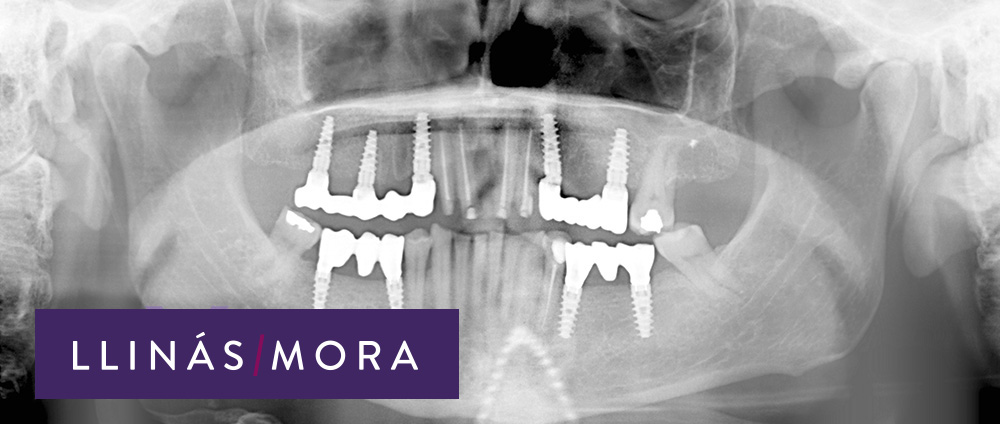

3. Cuatro meses después de comenzar el tratamiento

4. Combinación de implantes con regeneración ósea guiada y coronas ceramometalicas sobre dientes. Carillas de composite inferiores.